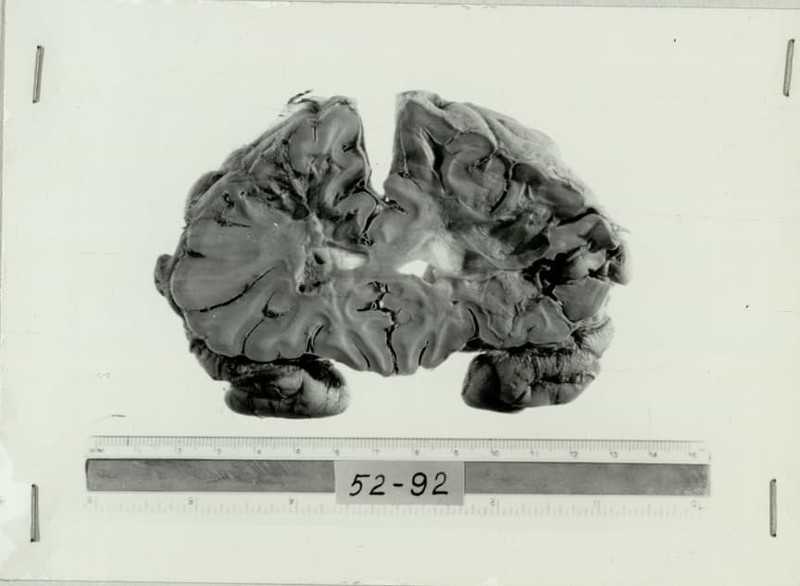

В среднем у 30 пациентов из 100 лоботомированных в той или иной степени проявлялась эпилепсия. Причем у части людей заболевание проявляло себя немедленного после разрушения лобной доли мозга, а у некоторых спустя несколько лет. До 3% пациентов умирали во время лоботомии от кровоизлияния в мозг… Фриман назвал последствия от подобного оперативного вмешательства синдромом фронтальной лоботомии, проявления которого часто были полярными. Многие становились несдержанными в пище и зарабатывали тяжелые степени ожирения. Раздражительность, циничность, грубость, неразборчивость в половых и социальных связях становились чуть ли не визитной карточкой «вылечившегося» пациента. Человек терял всякую способность к творческой деятельности и критическому мышлению.

К началу 40-х годов Фриман настолько усовершенствовал свою лоботомию, заключающуюся в отделении лобных долей мозга, что приноровился обходиться без сверления черепа. Для этого он вводил тонкий стальной инструмент в предлобные доли мозга через отверстие, которые предварительно им же и пробивал над глазом. Врачу оставалось только немного «пошарить» инструментом в мозгу пациента, разрушить лобные доли, вынуть окровавленную сталь, вытереть салфеткой и приступить к новой лоботомии. С началом войны в США потянулись тысячи психически надломленных ветеранов боевых действий, лечить которых было нечем. Классический психоанализ не особенно помогал, а химические методы лечения еще не появились.